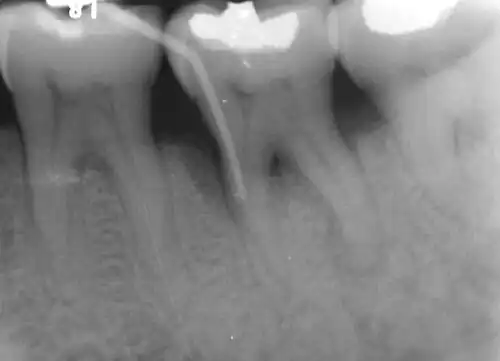

Diagnosis

Nabers probe is used to check for furcation involvement clinically. Recently, cone beam computerised technology (CBCT) has also be used to detect furcation.[5] Periapical and interproximal intraoral radiographs can help diagnosing and locating the furcation.

In dentistry, a furcation defect is bone loss, usually a result of periodontal disease, affecting the base of the root trunk of a tooth where two or more roots meet (bifurcation or trifurcation). The extent and configuration of the defect are factors in both diagnosis and treatment planning.[1]